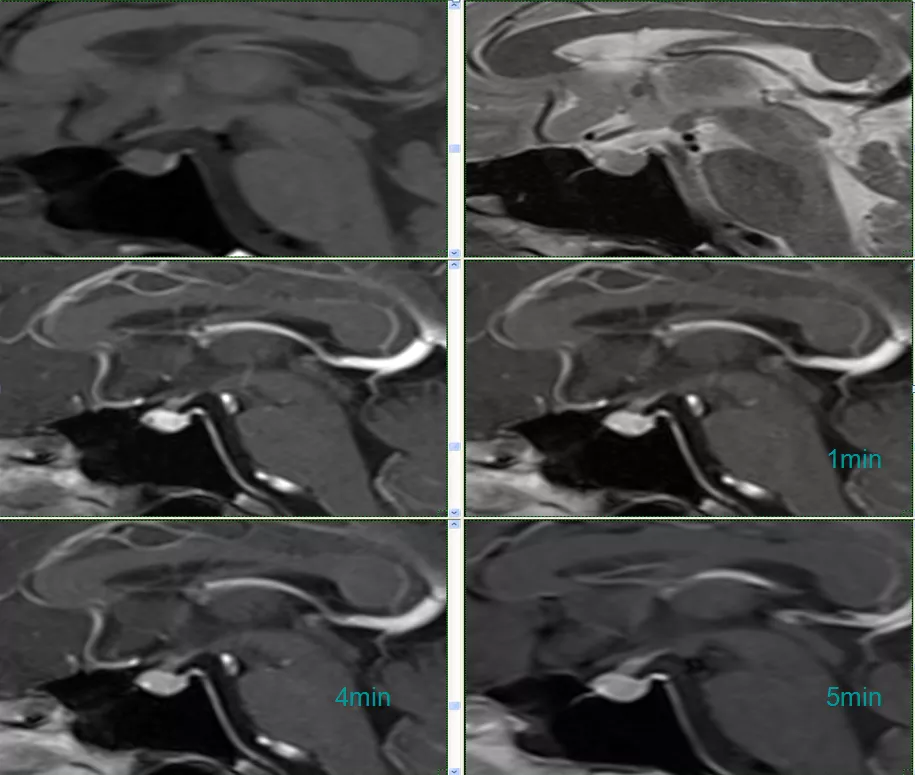

case 17:f/59y

看完 14 个病例,一起来认识这个表现多样的 Rathke’s囊肿

强化高峰出现较正常垂体腺晚,在团注造影剂后 3 min 内为最佳时间。强化持续时间长,必要时延迟扫描,延迟期肿瘤较垂体腺显著强化,信号高于正常垂体腺。动态强化很有必要。